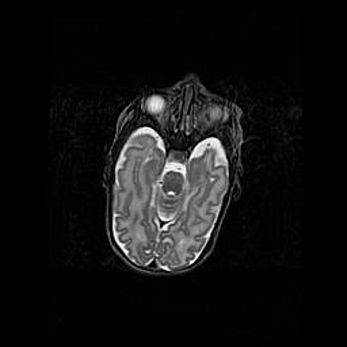

Сообщающаяся гидроцефалия. Кистозная энцефаломаляция головного мозга.

Возраст: 3 месяца 4 дня

Вес: 3100 г

Пол: женский

Окружность головы: 34 см

Срок гестации: 31 неделя

Кистозная энцефаломаляция головного мозга - одна из форм поражения головного мозга в детском возрасте. Характеризуется возникновением множественных и распространённых кист в коре, белом веществе и подкорковых образованиях головного мозга у плодов, новорождённых и детей раннего возраста. Развитие кистозной энцефаломаляции связано с внутриутробной асфиксией и гипотонией, родовой травмой, тромбозом синусов, пороками развития сосудов, инфекциями, сепсисом и другими причинами. Наиболее значимые инфекционные агенты: вирусы простого герпеса, цитомегалии, краснухи, токсоплазмы, энтеробактерии, золотистый стафилококк и другие.